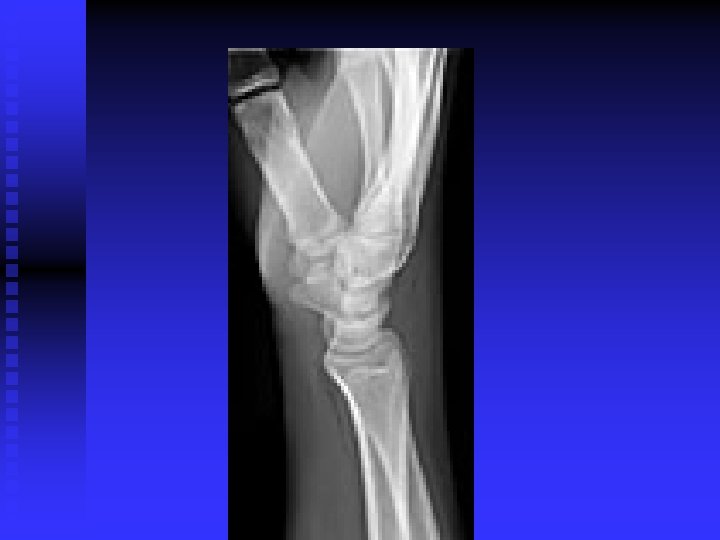

WRIST AND HAND

Carpal Tunnel Syndrome n n Median nerve compression within the carpal tunnel is the most common peripheral nerve entrapment syndrome. Any condition that decreases the cross sectional area of the carpal tunnel or increases the volume of its contents may cause the pathology. EX: lunate dislocation; distal radius fracture, sustained flexion or extension postures, fluid retention, synovitis